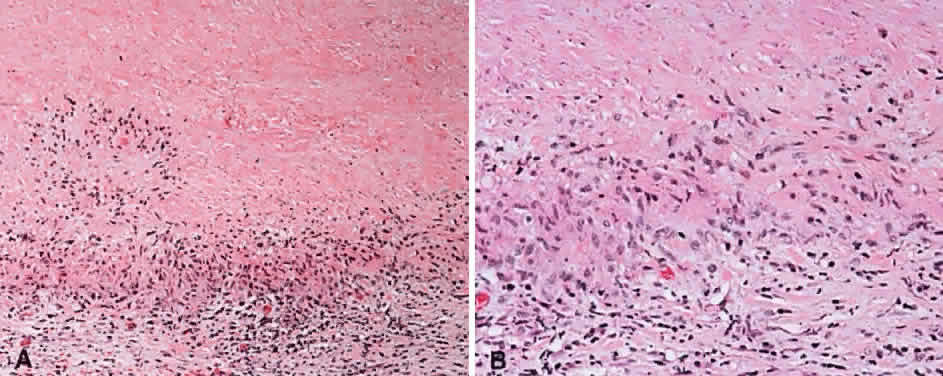

Numerous attempts have been made to classify lymphoid processes for clinical management and prediction of prognosis. Early classifications included only disease localized to the lymph node, which made classification of extranodal disease difficult and inaccurate. The Rappaport classification, first developed in 1956 and then modified in 1978, attempted to categorize lymphomas in two ways, first, using cytologic characteristics identified by conventional stains, and second, distinguishing between the follicular and diffuse growth pattern histologically38,39 (Table 3). The distinction of nodular, or follicular, and diffuse growth was considered useful because of the generally indolent nature of follicular growth, in which the tumor cell aggregates resemble germinal centers and disrupt the normal architecture of the node, compared with the appearance of diffuse growth, in which the lymph node is completely obliterated by a dense monotonous sheet of lymphocytes. In subsequent years, however, it was found that the descriptive growth pattern and cytogenetic characteristics of the Rappaport system did not predict prognosis reliably and were biologically inaccurate. The complexity of correlating degrees of differentiation, mitotic activity, and cytologic characteristics to prognosis have made lymphomas difficult to classify and have led to subsequent systems. The second system, proposed by Lukes-Collins in 1974, classifies lymphoma histologically according to its normal counterpart B-cell, T-cell, or null cell origin40,41 (see Table 3). Histologically, cells may appear small cleaved, large cleaved, small noncleaved, or large noncleaved, depending on the stage of B-cell arrest during normal transformation to immunoblast. Ninety percent of lymphomas are of B-cell origin, and the null cell also usually is of B-cell origin, although 10% may originate from T cells or histiocytes.42,43 Burkitt's lymphoma, the only lymphoma common in children, is a B-cell variant with a background of reactive histiocytes. As a result of histologic classification by Lukes-Collins, 76% of histiocytic lymphomas according to the Rappaport system were found to be not of histiocytic origin but of lymphocytic origin.40,44 The third system, the Working Formulation devised by the National Cancer Institute in 1982, attempted to predict prognosis by grouping lymphoma according to natural history, response to therapy, and overall survival.45 Three broad categories were established in terms of 5-year survival rates, the low-grade with a 50% to 70% survival rate, intermediate with 35% to 45%, and high grade with 23% to 32% (see Table 3). Orbital reactive hyperplasia, a relatively low-grade lesion, can be associated with systemic disease, whereas malignant or high-grade orbital lymphomas may be isolated findings. The Ann Arbor Staging Classification for Hodgkin's and non-Hodgkin's lymphomas was developed to stage disease based on systemic areas of involvement as a means of establishing a baseline for treating disease and following clinical progression46 (Table 4). Histologic classification, however, has been recognized as more useful than localization in the clinical management of nonHodgkin's lymphoma.47